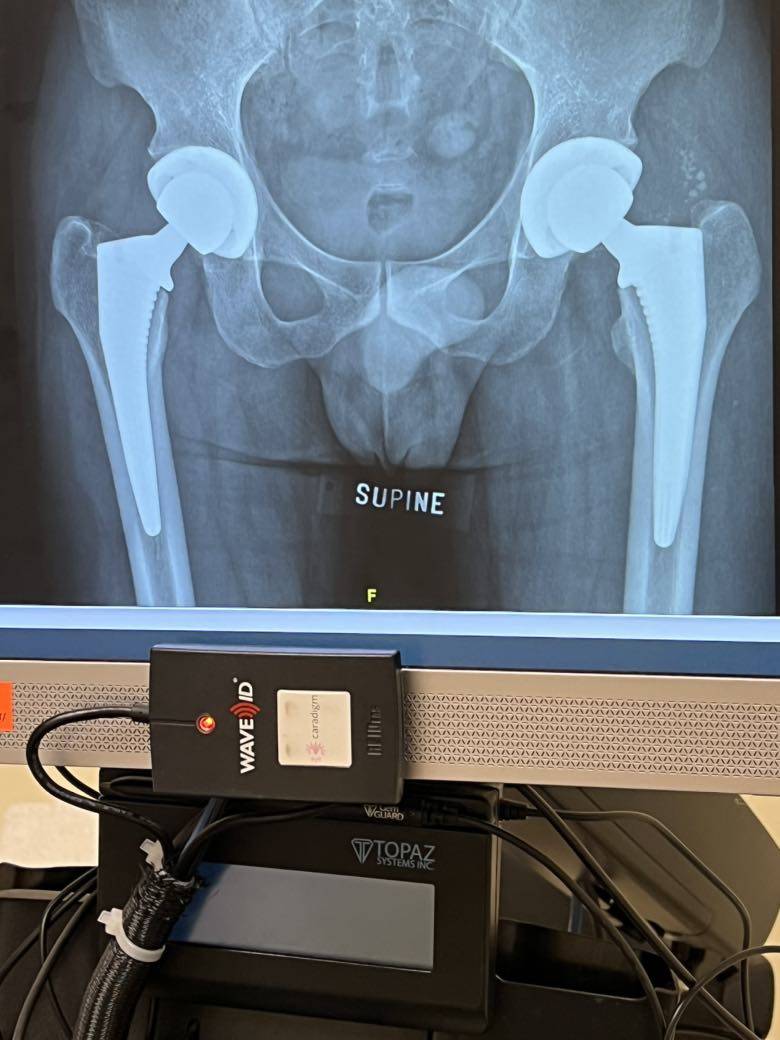

双侧置换完成

2020年3月查出股骨头坏死到2021年8月彻底失去行动能力,其实2月份就已经右侧4期左侧3期晚期。8月24换的右侧,10月28换左侧。 不要问我材料和价钱,因为我也不是特别清楚。